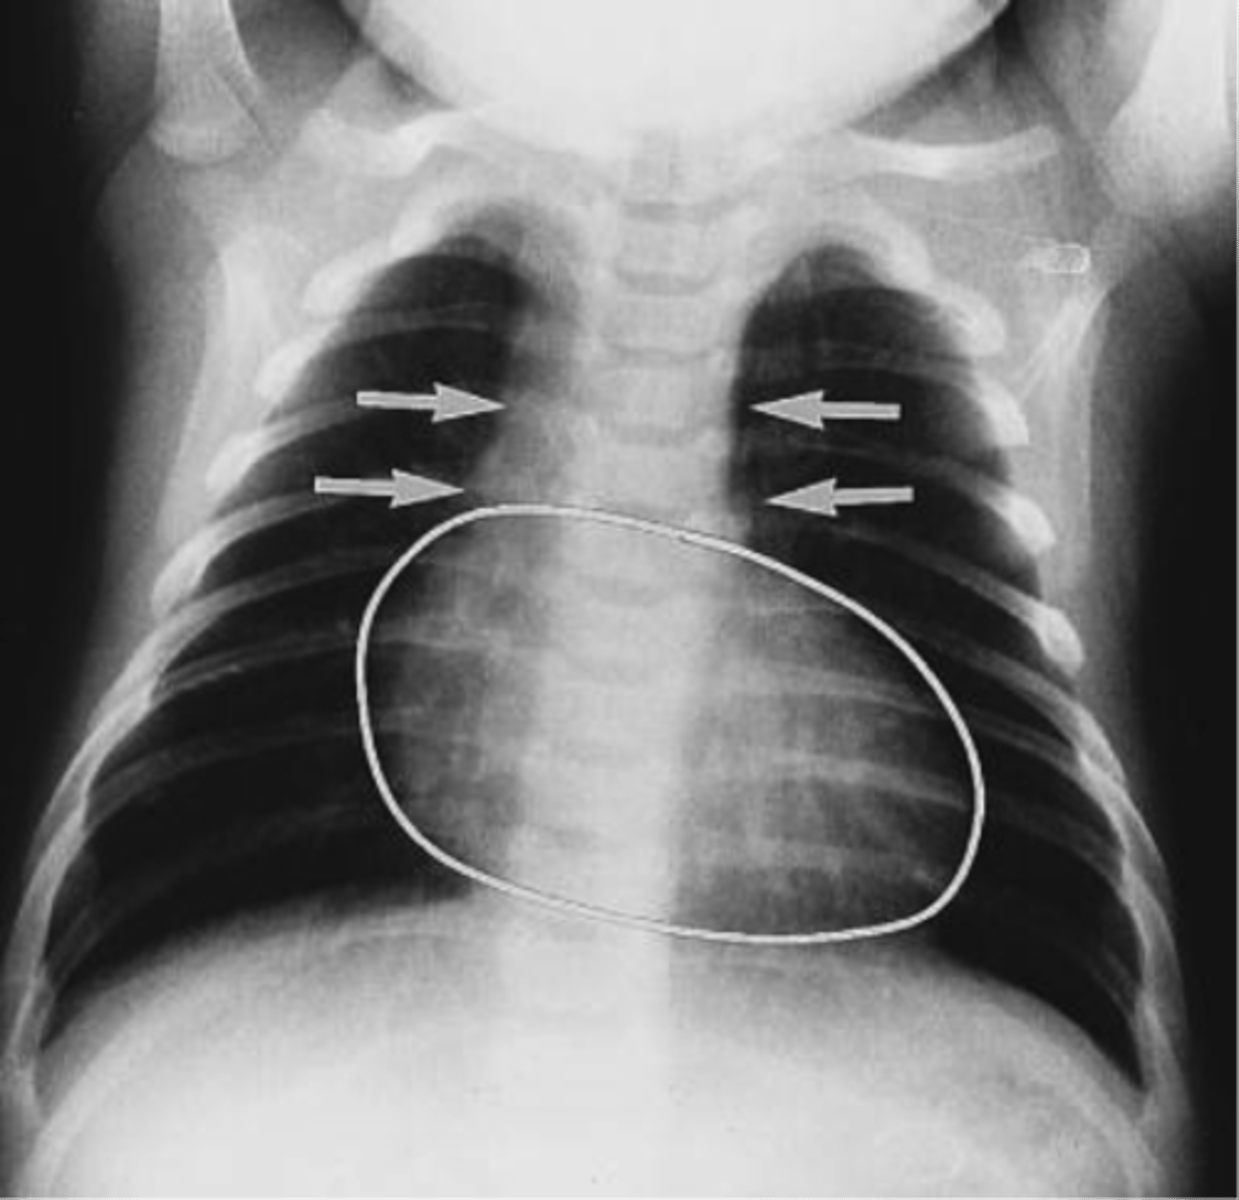

___ is a cyanotic congenital heart defect characterize by left axis deviation on electrocardiogram and DEC pulmonary markings on CXR due to hypoplasia of the RV and pulmonary outflow tract.

Tricuspid valve atresia

- left axis deviation